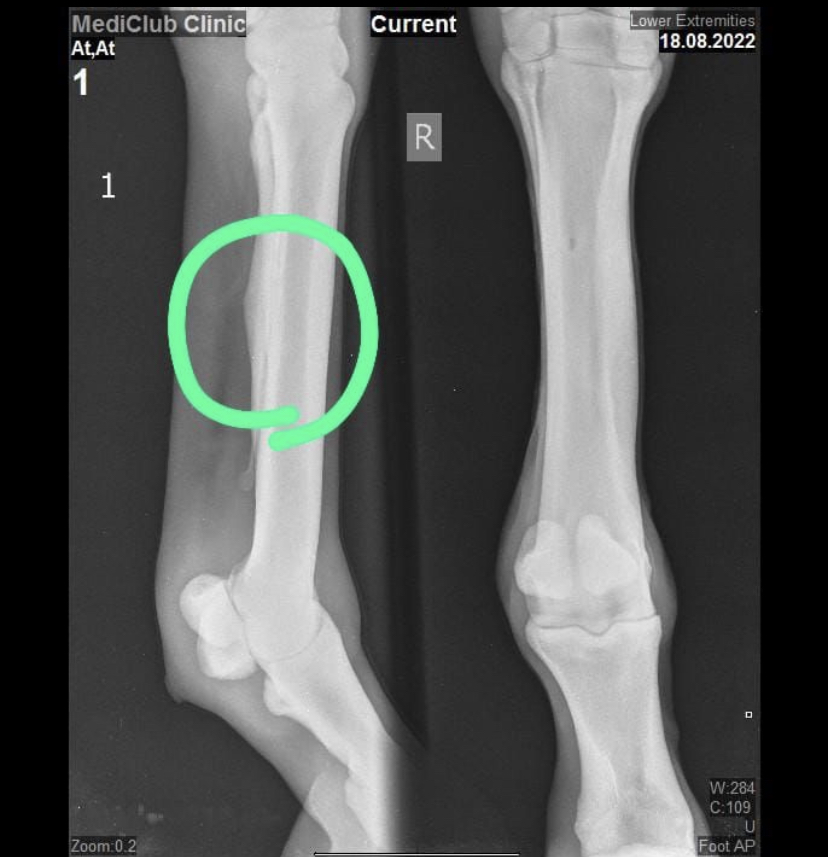

Здравствуйте.В четверг утром работники увидели, что у коня опухла левая нога выше запястья.Дотрагиваться до ноги он не давал, отек теплый.Врач еще не доехал, но с моих прошлых постов вы можете понять, что врачи у нас 0.Конь в легком тренинге + учится прыгать, день до этого отека он стоял, работники предполагают, что либо его кто-то укусил, либо ударился в деннике.Укололи два укола и мажут ихтиол, не знаю даже зачем, по-моему нужно отливать и мазать что-то типо троксевазина от отеков.Ест, не вялый, шагают его несколько раз в день.Когда приедет врач не ясно вообще.Прошло два дня и отек чуть спал.Что можно сделать в таком случае и какие предложение, что это может быть?Напомню, что у коня правая нога в районе пясти немного искривлена, сделали рентген и скорее всего он сломал грифельную кость, потом это лечили выжиганием(сразу обе ноги), на ногу не жаловался после покупки, просто часто спотыкается.Конь знакомых, они вообще не разбираются и не знают, что делать.